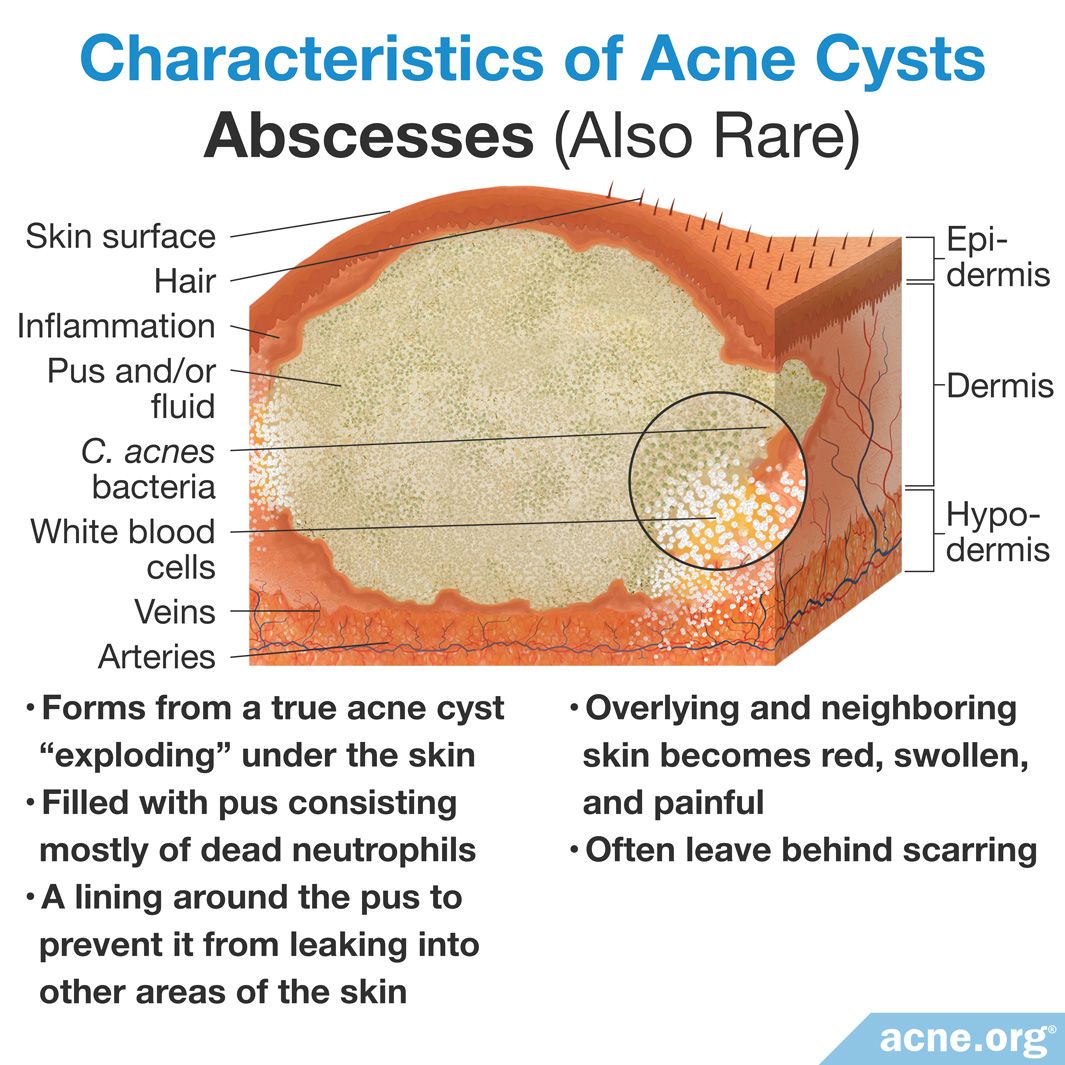

What Is an Acne Cyst? – Acne.org